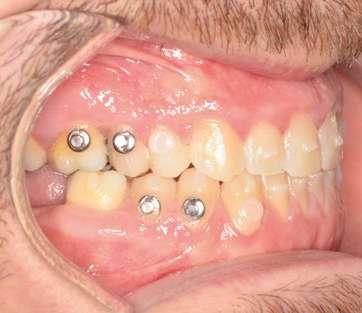

Fase 1: disyunción con MARPE

Tras colocar la anestesia palatina infiltrativa, el disyuntor osteo-soportado con tornillo hexagonal, se fijó de forma segura mediante los mini-tornillos utilizando un contra-ángulo de baja velocidad. Ese mismo día, se inició la expansión con pauta de 1 vuelta al día (0,16 mm por vuelta). Tras 43 días, se apreció la apertura de diastema inter-incisal y se continuó dando vueltas durante 18 días más hasta conseguir la corrección de la mordida cruzada posterior (Ilustración 5).

El paciente fue instruido en la higiene del dispositivo para evitar inflamación gingival y se realizaron controles rutinarios cada dos semanas. Al finalizar el procedimiento de expansión, el paciente fue monitoreado durante 75 días.

Evidencia clínica y radiográfica de la expansión:

 Separación visible de incisivos centrales, indicativa de apertura de la sutura palatina.

 Expansión confirmada mediante superposición de los modelos maxilares digitales previos y posteriores al tratamiento mediante MARPE (Ilustración 6). Se obtuvo un aumento transversal del 5,14 mm a nivel de los primeros molares.

Ilustración 5. Fotografías intraorales tras la disyunción con MARPE.